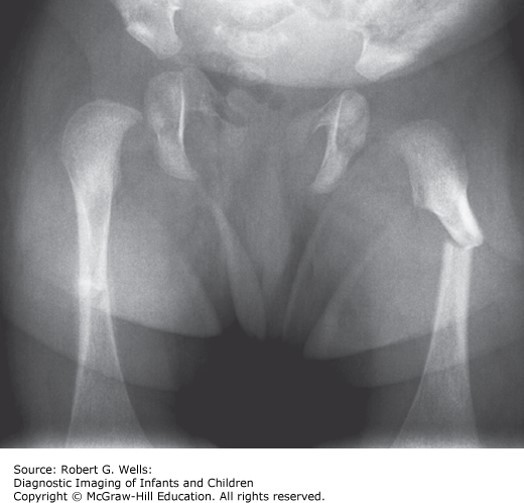

A 14-month-old boy presents with refusal to bear weight on his right leg after falling off the bed.

A 14-month-old boy presents with refusal to bear weight on his right leg after falling off the bed. X-rays demonstrate a midshaft femur fracture. Medical records demonstrate prior visits for a wrist fracture and a tibial fracture over the past 3 months. Physical examination reveals multiple bruises. Skeletal survey demonstrates healing right distal radius and right spiral tibial fractures, but no other healing or new fractures. Head magnetic resonance imaging (MRI) does not reveal any intracranial injury and there are no retinal hemorrhages.

The correct answer is “D.” Concerns regarding osteogenesis imperfecta are frequently entertained in cases of unusual or frequent fractures and may be mistaken for nonaccidental trauma. Numerous genetic causes have been identified, most commonly in the formation of bone involving collagen (COL1A1, COL1A2, and others). Vitamin D levels are normal. Inheritance patterns of the genetic abnormalities include autosomal dominant, recessive, and X-linked forms, but current classification remains based on phenotype. Type I, or nondeforming, is the mildest, and patients typically achieve normal height. Type II is lethal in the perinatal period. Type III often presents at birth with frequent fractures and results in progressive deformity, and type IV is the moderate form. Type V involves ossification of the interosseous membrane, hypertrophic callus formation, or both. Blue sclera are common in types I and III, but individuals with type IV often have white sclera. Patients often have triangular facies and macrocephaly, and may have hearing loss. Short stature, easy bruising, and joint hypermobility may also occur. X-rays often demonstrate osteopenia or wormian bones of the skull.